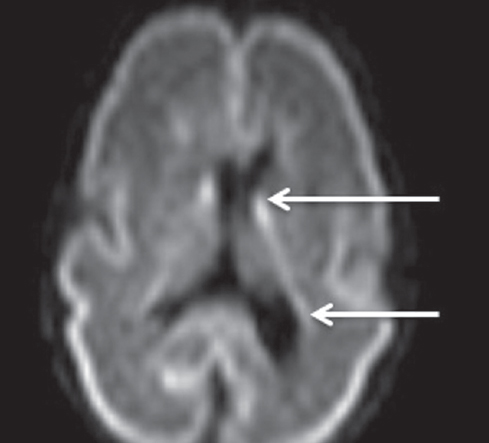

Patterns of neuroplasticity and cerebral maturation in preterm neonate can be assessed by MRI and cranial ultrasound. The score system of brain maturation includes the account of germinal matrix (GM) regression by MRI. The GM regression can be considered as pattern of neuroplasticity. There have been investigated the changes of neuroplasticity pattern or GM regression in preterm neonates with extremely low birth weight (ELBW) without intragerminal/intraventricular hemorrhages (n = 21). It is believe that the main causes of impair of GM are the intragerminal hemorrhages and hypoxia. The methods of study were cranial ultrasound (CU) and MRI. The measurement of GM was carried out by CU in anterior horn of the lateral ventricles of neonates in the study group (25-29 weeks). It was detected the GM regression in preterm neonates with increasing age, and complete GM regression to 30 week. MRI has been performed in 15 neonates from the study group on 27-38 weeks age with using the common pulse sequences – T1 WI, T2 WI and Flair. GM was detected by MRI up to 34 weeks inclusive by using the additional pulse sequence – DWI. By using common pulse sequences the GM was visualized up to 32 weeks age. Furthermore there has been pathological examination of GM in anterior horn of lateral ventricle in dead neonates from the study group (n = 3). We revealed the thickness reduction of GM in the lateral ventricles with increasing age of the dead neonates. Also we identified the delay of the GM reduction in two dead neonates 36-38 weeks age (post conceptual age) what may indicate the disorder of neuroplasticity in those preterm neonates. The performed study showed the capability of CU and MRI in examination of neuroplasticity in preterm neonates.